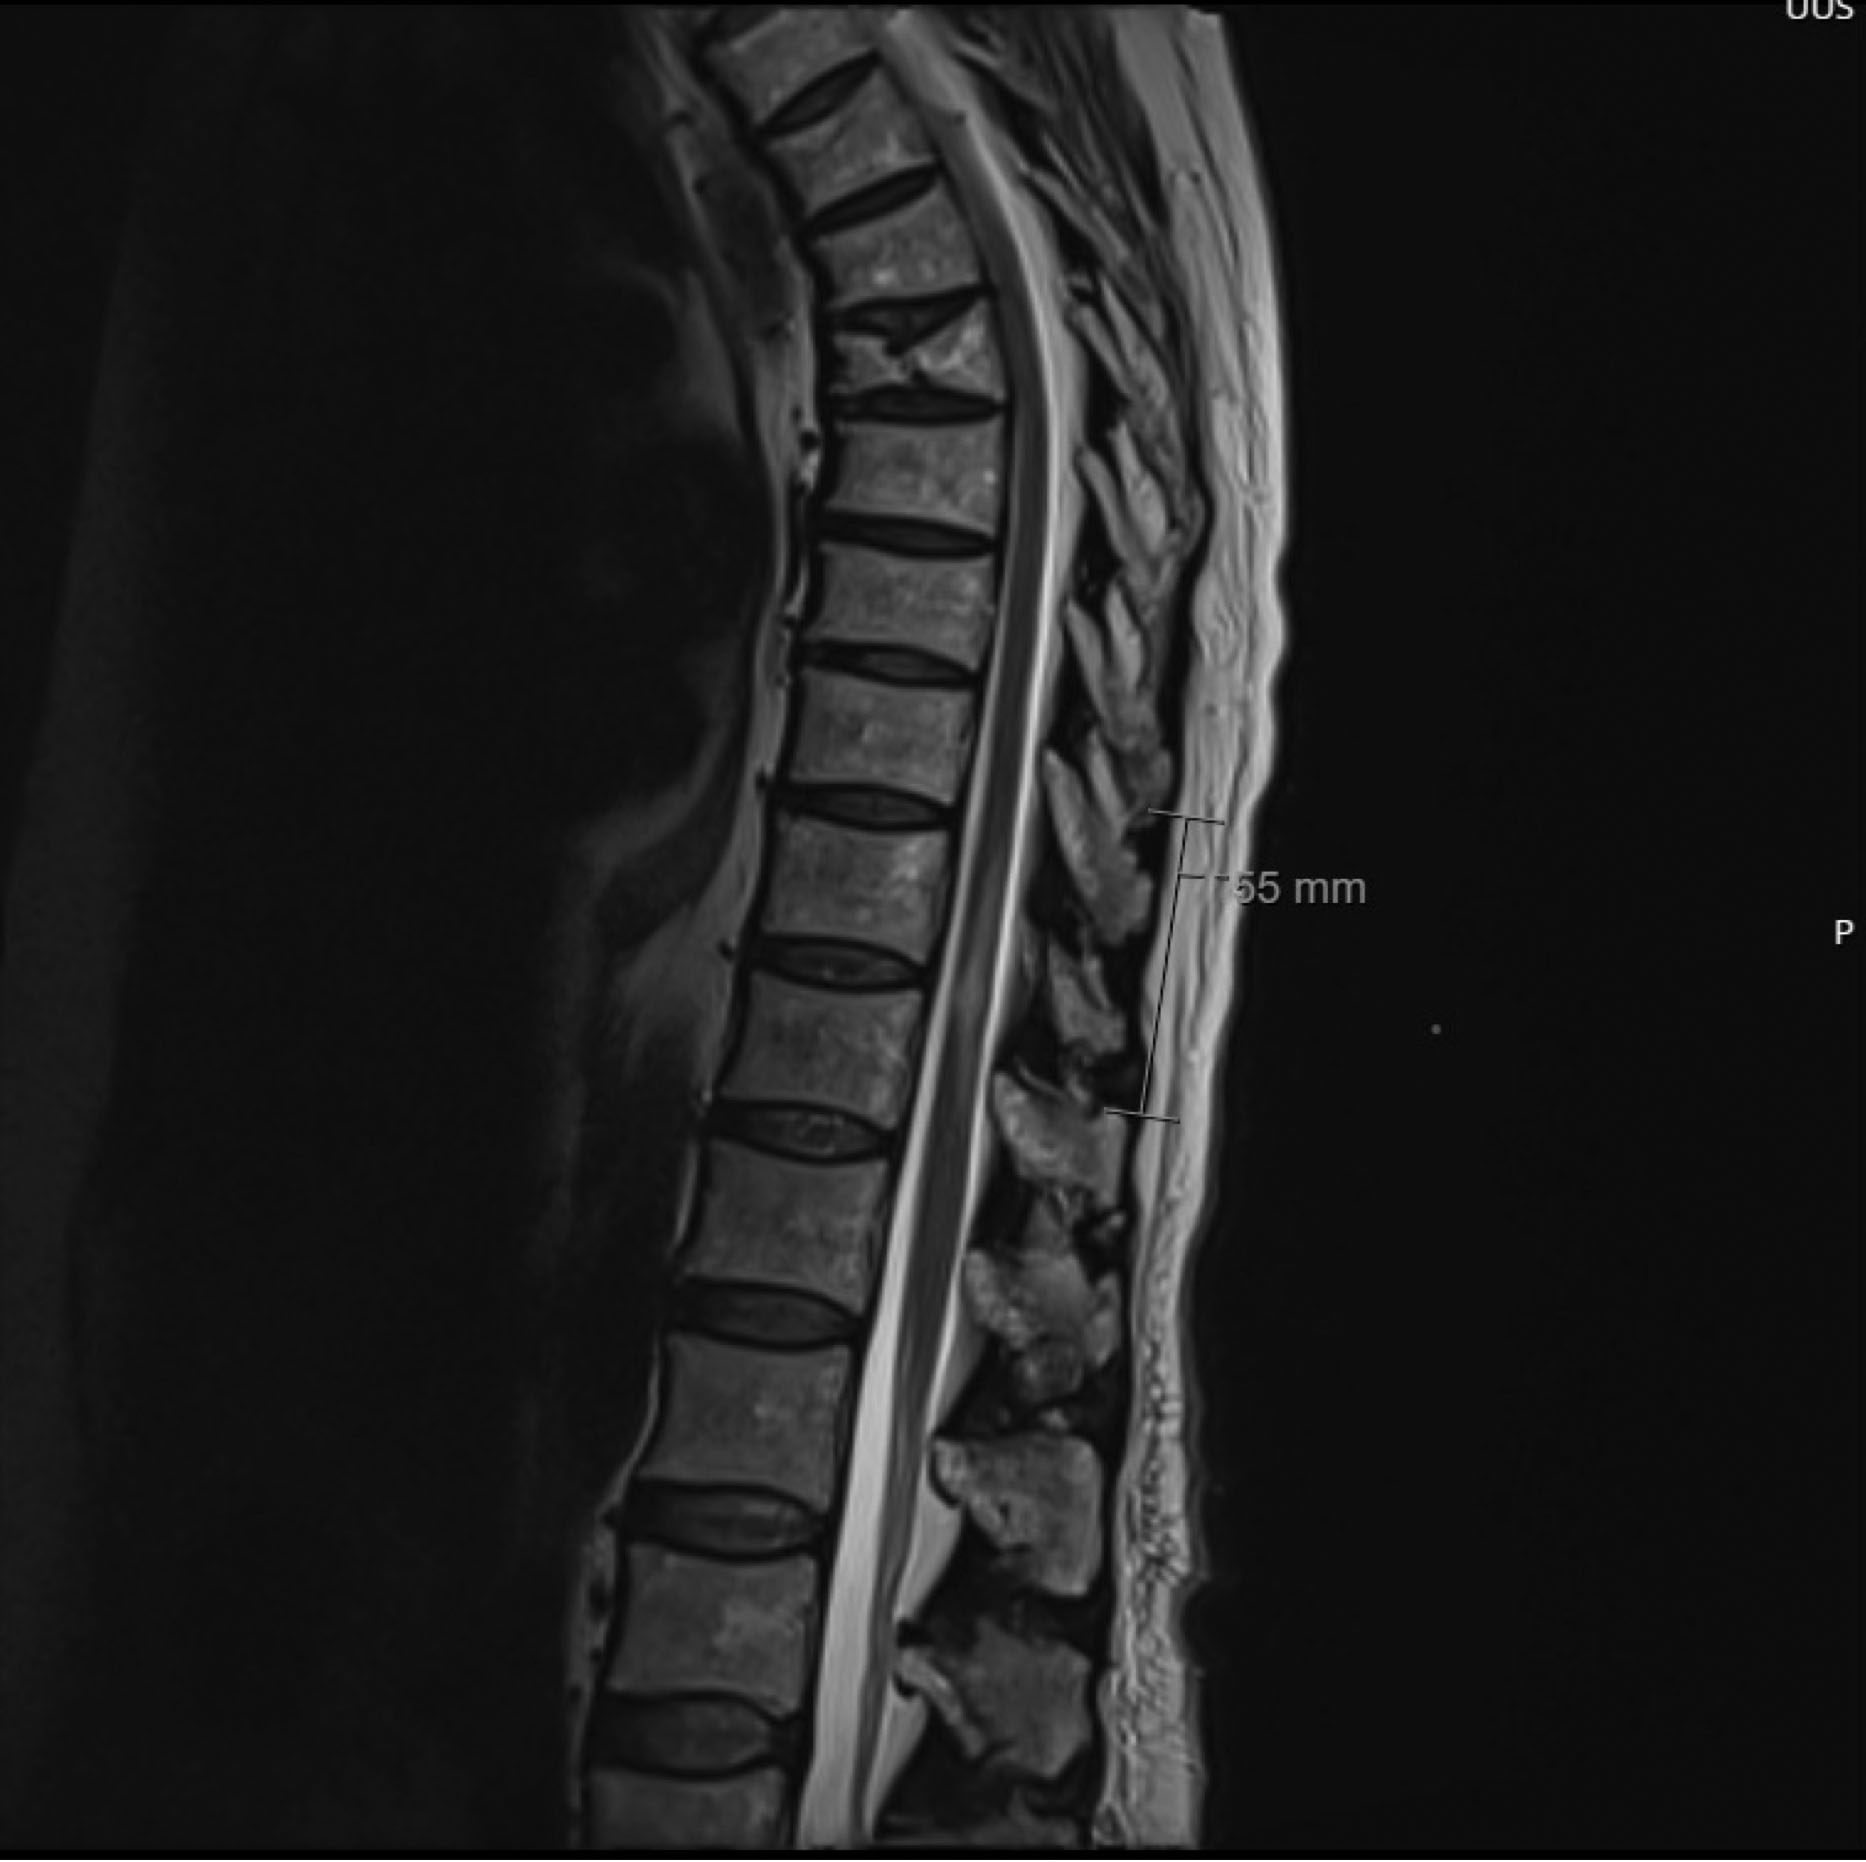

En kvinne i 80-årene ble lagt inn med akutt funksjonssvikt og fall. Fra tidligere var pasienten hjemmeboende, selvhjulpen og aktiv utendørs. Pasienten hadde kjent perifer karsykdom og kronisk obstruktiv lungesykdom (kols) grad 2, men var fysisk og kognitivt velfungerende. I uken før innleggelse hadde pasienten redusert allmenntilstand og økende falltendens. Hun beskrev sviktfølelse i begge bena, smerter i kneleddene og ustøhet. Pasienten synkoperte på innleggelsesdagen og ble liggende på gulvet uten mulighet til å komme seg opp selv. Hun var forvirret, hadde latens i talen og ordletingsvansker. Ved klinisk undersøkelse i akuttmottaket var pasienten afebril med temperatur på 36,6 °C, blodtrykket var 109/84 mmHg og pulsen var regelmessig på 76 slag/min. CRP var på 7 mg/L (referanseområde < 4 mg/L) og leukocytter på 9,6 × 109/L (3,5–10,0 × 109/L). Man fant hyponatremi på 128 mmol/L (137–144 mmol/L), plasmaosmolalitet på 267 mmol/kg (281–295 mmol/kg), urinosmolalitet på 505 mmol/kg (200–800 mmol/kg) og urinnatrium på 55 mmol/L. Nyrefunksjonen var normal med kreatinin på 60 μmol/l (45–90 μmol/L). Pasienten hadde urinretensjon med 833 ml urin i blæren og positiv urinstix. Hyponatremien ble vurdert å skyldes for høy sekresjon av ADH, såkalt SIADH-syndrom (syndrome of inappropriate secretion of anti-diuretic hormone), og hun ble behandlet med væskerestriksjon. I tillegg ble det startet behandling med pivmecillinam 200 mg × 3 peroralt i tre dager. Pasienten ble lagt på observasjonsposten det første døgnet. På bakgrunn av ordletingsvansker, talelatens og nedsatt kraft i venstre ben, ble det tatt CT caput, som ikke viste tegn til akutt patologi. Siden arteriell blodgass viste lett hypokapni 4,1 kPa (4,7–6,0 kPa) og hypoksemi 7,9 kPA (10–14 kPa), ble pasienten utredet for lungeemboli med CT toraks. Det ble påvist perifere lungeembolier, og pasienten ble behandlet med dalteparin 5000 IE subkutant × 2. Pasienten ble på dag 2 overflyttet til akuttgeriatrisk sengepost for videre tverrfaglig utredning. På dag 4 ble det observert kraftsvikt i venstre ankel. Dagen etter viste nevrologisk undersøkelse uttalt parese over alle ledd i venstre ben (grad 2/5) samt nedsatt sensibilitet for stikk og temperatur i hele høyre ben opp til hoftekammen og i distalt venstre ben opp til midten av leggen. Hun hadde normale reflekser i kne og ankel, men invertert plantarrefleks i venstre fot og dorsale napp i høyre fot, forenlig med sentrale pareser i begge ben. Pasienten kunne ikke forflytte seg uten hjelp, og hadde allerede i akuttmottaket fått påvist urinretensjon. Det var nå også tilkommet obstipasjon. MR caput på dag 5 viste ingen tegn til akutt hjerneinfarkt, og i samråd med vakthavende nevrolog ble det på dag 6 tatt MR totalcolumna som viste T2-høysignalforandringer i TH11–TH12-nivå med en størrelse på 5 cm × 0,6 cm (figur 1 og 2), forenlig med enten infarkt eller myelitt. Pasienten hadde pågående behandling med antikoagulasjon grunnet lungeemboli, og spinalpunksjon var først mulig tre dager etterpå. Spinalvæsken var gullig, blakket og med leukocytter på 833 × 106/L (< 5 × 106/L). Vi mistenkte infeksiøs myelitt som aktuell diagnose, og det ble startet behandling med ceftriakson intravenøst 2 g × 1 og aciklovir intravenøst 1000 mg ×3. Det ble påvist DNA fra varicella-zoster-virus (VZV) i spinalvæske samme dag (dag 9) og ceftriakson ble seponert. Pasienten hadde ingen smerter. På dag 11 ble hun flyttet til infeksjonsmedisinsk avdeling.